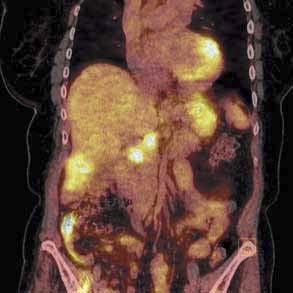

wego stopnia zaawansowania, jak i ognisk przerzutowych. Podstawowym radiofarmaceutykiem stoso-

syglukoza (18F-FDG). Zastosowanie analogu glukozy

reakcji w produkcji adenozynotrifosforanów (ATP)glukozy jest proporcjonalny do stopnia biologicznej 18F-FDG transportowana jest

sokinazy. Badanie PET jest szczególnie przydatne

zmian chorobowych stwierdzanych w innych technikach obrazowych, nowotworowych,

badania u chorego z podejrzeniem choroby

badanie u chorego po operacji stanowi badanie z wyboru w ponownej ocenie stopnia zaawansowa-